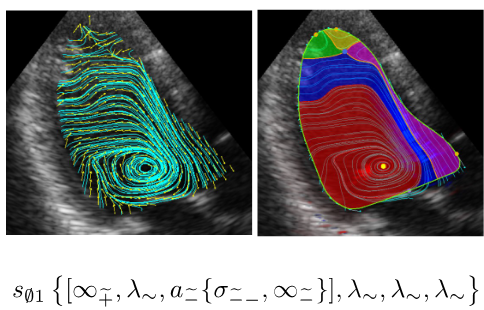

本研究グループは、心血流エコーやMRIから得られる流線画像データに対して適用できるTFDAの数学理論を完成しました。これを用いると、心臓超音波VFM(Vector Flow Mapping)によって得られる健常例の左室心尖部の長軸断面で得られる収縮期血流画像(下図左パネル)から、特徴的な位相構造を抽出して数学的に分類し、さらにそのパターンに固有の文字列表現(COT表現:下図下)を割り当てることができました。このCOT表現後に一部の特定文字列が心臓血流内部の特定渦領域(下図右パネルの赤色部分)を表現するので、これを「位相的渦構造」として、数学的にも曖昧さなく定めることができます。このような心臓血流エコー画像をトポロジカルデータ解析する技術開発ができたのは世界初です。この結果、これまで明確な定義がなかった心臓血流が作り出す「渦流」に、TFDAは「位相的渦構造」と呼ばれる新しい概念を定義することに成功しました。さらに、このことにより、渦構造と心臓のポンプとしての機能や心疾患の病態を位相的渦構造で評価できるようになりました。

図1 (左上)心エコーVFMのデータ

(右上)TFD解析によって得られた渦血流領域(赤い領域)

(下)TFD解析で得られるCOT表現文字列

※画像は超音波画像血流解析ソフトiTEcho®(研究用)で作成した物です